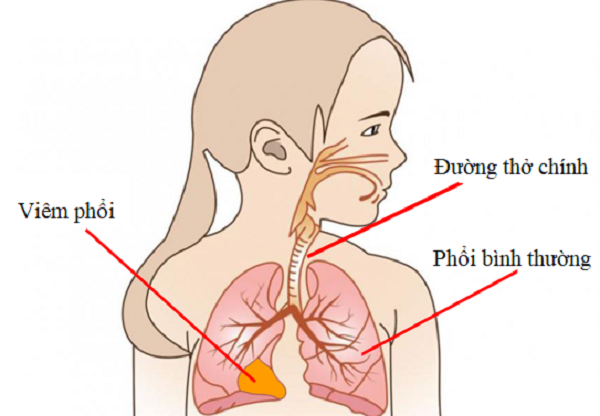

Viêm phổi ở trẻ có triệu chứng gì?

SKĐS - Viêm phổi ở trẻ là vấn đề thường gặp khiến cha mẹ lo lắng. Bệnh có thể xuất hiện khi trẻ đang bị một đợt ho hoặc cảm cúm, sau khoảng vài ngày có thể tiên triển thành viêm phổi.

Nếu không được phát hiện sớm và chữa trị kịp thời, viêm phổi có thể là nguyên nhân gây tử vong cao ở nhóm trẻ dưới 5 tuổi.

Viêm phổi ở trẻ em là tình trạng nhiễm trùng đường hô hấp cấp nặng, gây tổn thương nhu mô phổi dẫn đến suy hô hấp do rối loạn trao đổi khí, là nguyên nhân hàng đầu gây tử vong trong các bệnh về đường hô hấp ở trẻ em. Bệnh có thể gặp ở mọi lứa tuổi, tuy nhiên trẻ dưới 2 tuổi hay gặp hơn.

Tổ chức Y tế thế giới và UNICEF ước tính, năm 2015, khoảng 16% trẻ tử vong dưới 5 tuổi là do viêm phổi. Theo một nghiên cứu, tỷ lệ bị viêm phế quản phổi và viêm phổi nhập viện chiếm 25% trong tổng số trẻ bị nhiễm khuẩn đường hô hấp.

Bệnh viêm phổi ở trẻ xảy ra quanh năm nhưng hay gặp vào mùa thu đông và đầu xuân. Viêm phổi chủ yếu lây truyền qua đường hô hấp. Vi khuẩn, virus trú ngụ ở mũi họng và được phát tán khi trẻ ho, hắt hơi, chảy mũi. Trẻ sơ sinh có thể bị bệnh do lây qua đường máu ở giai đoạn khi sinh và ngay sau sinh.